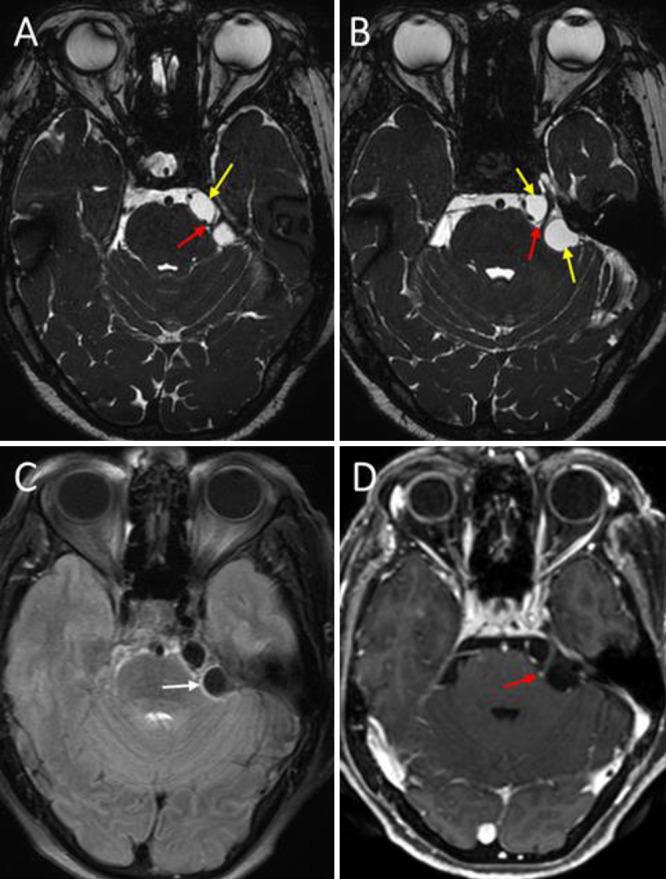

Trigeminal neuralgia (TN) is a frequent neurosurgical problem negatively influencing the quality of life of patients. The standard surgical treatment is microvascular decompression for primary cases and decompression of the mass effect, mainly tumors, for secondary cases. Neurocysticercosis (NCC) in the cerebellopontine angle is a rare etiology of TN. The authors report a case in which NCC cysts around the trigeminal nerve coexisted with a vascular loop, which compressed the exit of the trigeminal nerve from the pons.

A 78-year-old woman presented with a 3-year history of persistent severe pain in the left side of her face, refractory to medical treatment. On gadolinium-enhanced magnetic resonance imaging, cystic lesions were observed around the left trigeminal nerve and a vascular loop was also present and in contact with the nerve. A retrosigmoid approach for cyst excision plus microvascular decompression of the trigeminal nerve was successfully performed. There were no complications. The patient was discharged without facial pain.

三叉神经痛(TN)是一个常见的神经外科问题,对患者的生活质量有负面影响。标准的外科治疗方法是对原发性病例进行微血管减压,对继发性病例进行主要针对肿瘤的占位效应减压。小脑脑桥角的神经囊虫病(NCC)是TN的一种罕见病因。作者报告了一例三叉神经周围的NCC囊肿与血管袢共存的病例,该血管袢压迫了三叉神经从脑桥的出口。

一名78岁女性,有3年左侧面部持续剧痛病史,药物治疗无效。在钆增强磁共振成像上,观察到左侧三叉神经周围有囊性病变,并且存在一个血管袢并与神经接触。成功实施了乙状窦后入路囊肿切除术加三叉神经微血管减压术。无并发症。患者出院时面部疼痛消失。